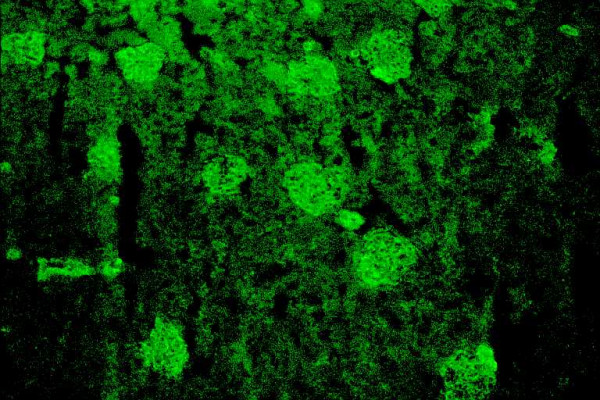

自身免疫性肝炎(AIH)是一种慢性肝脏坏死性炎症疾病,其特征是高丙种球蛋白血症、特征性自身抗体、与 HLA DR3 或 DR4 相关以及对免疫抑制治疗的良好反应。病因不明。在没有病毒、代谢、遗传和中毒性慢性肝炎或肝损伤病因的情况下,检测非器官和肝脏相关的自身抗体仍然是诊断该病的标志。本文报告了 AIH 目前的分类以及在该疾病中发现的几种自身抗体/目标自身抗原。此外,还阐述了这些标记物在鉴别诊断和 AIH 发病机制研究中的重要性。AIH 可细分为两大类型:AIH 1 型(AIH-1)和 AIH 2 型(AIH-2)。AIH-1 型的特征是检测到平滑肌自身抗体(SMA)和/或抗核抗体(ANA)。检测抗中性粒细胞胞浆自身抗体(ANCA)、抗淀粉样糖蛋白受体抗体(抗ASGP-R)和抗可溶性肝抗原或肝胰腺抗体(抗SLA/LP)可能有助于鉴别ANA/SMA血清阴性的患者。AIH-2的特点是存在针对肝脏和肾脏微粒体抗原的特异性自身抗体(抗LKM-1型或不常见的抗LKM-3型)和/或针对肝脏胞浆1抗原的自身抗体(抗LC1)。在一些慢性丙型肝炎(HCV)和慢性丁型肝炎(HDV)患者中也能检测到抗 LKM-1 和抗 LKM-3 自身抗体。细胞色素 P450 2D6 (CYP2D6) 已被证实是 AIH-2 和 HCV 感染中抗 LKM-1 自身抗体的主要靶抗原。最近有令人信服的数据表明,CYP2D6 在肝细胞表面的表达表明,抗 LKM-1 自身抗体在肝损伤中起着致病作用。UDP-糖醛酸转移酶家族 1 已被确定为抗 LKM-3 的靶自身抗原。因此,区分 AIH 和慢性病毒性肝炎(尤其是 HCV)尤为重要。最近,抗SLA/LP和抗LC1自身抗体的分子靶点被确定为一种50 kDa的UGA抑制tRNA相关蛋白和一种肝脏特异性酶--甲氨蝶呤环化酶。抗ASGP-R和抗LC1自身抗体似乎与疾病的严重程度和对治疗的反应密切相关,这表明这些自身抗体对肝细胞损伤具有致病作用。但一般来说,自身抗体不应被用于监测治疗、预测 AIH 的活动性或预后。最后,本文还介绍了一种特殊形式的 AIH,即自身免疫性多内分泌病-念珠菌病-外胚层营养不良综合征(APECED),它可能发生在一些患有罕见遗传综合征的患者身上。肝微粒体自身抗体(抗-LM)是在作为 APECED 疾病组成部分的 AIH 中检测到的特异性自身抗体,也可在二氢嗪诱发的肝炎病例中检测到。在与 APECED 相关的 AIH 和二氢嗪诱导的肝炎中,细胞色素 P450 1A2 被确定为抗 LM 自身抗体的靶自身抗原。后者可能表明,类似的自身免疫致病机制可导致易感个体的肝损伤,而与原发性缺陷无关。自身抗原-自身抗体复合物的特征描述仍然是一种极具吸引力的重要工具,可用于获得正确的诊断,并深入了解肝脏耐受性是如何被放弃以及 AIH 是如何产生的这一尚未解开的谜团。

Autoimmune hepatitis (AIH) is a chronic necroinflammatory disease of the liver characterized by hypergammaglobulinemia, characteristic autoantibodies, association with HLA DR3 or DR4 and a favorable response to immunosuppressive treatment. The etiology is unknown. The detection of non-organ and liver-related autoantibodies remains the hallmark for the diagnosis of the disease in the absence of viral, metabolic, genetic, and toxic etiology of chronic hepatitis or hepatic injury. The current classification of AIH and the several autoantibodies/target-autoantigens found in this disease are reported. Current aspects on the significance of these markers in the differential diagnosis and the study of pathogenesis of AIH are also stated. AIH is subdivided into two major types; AIH type 1 (AIH-1) and type 2 (AIH-2). AIH-1 is characterized by the detection of smooth muscle autoantibodies (SMA) and/or antinuclear antibodies (ANA). Determination of antineutrophil cytoplasmic autoantibodies (ANCA), antibodies against the asialoglycoprotein receptor (anti-ASGP-R) and antibodies against to soluble liver antigens or liver-pancreas (anti-SLA/LP) may be useful for the identification of patients who are seronegative for ANA/SMA. AIH-2 is characterized by the presence of specific autoantibodies against liver and kidney microsomal antigens (anti-LKM type 1 or infrequently anti-LKM type 3) and/or autoantibodies against liver cytosol 1 antigen (anti-LC1). Anti-LKM-1 and anti-LKM-3 autoantibodies are also detected in some patients with chronic hepatitis C (HCV) and chronic hepatitis D (HDV). Cytochrome P450 2D6 (CYP2D6) has been documented as the major target-autoantigen of anti-LKM-1 autoantibodies in both AIH-2 and HCV infection. Recent convincing data demonstrated the expression of CYP2D6 on the surface of hepatocytes suggesting a pathogenetic role of anti-LKM-1 autoantibodies for the liver damage. Family 1 of UDP-glycuronosyltransferases has been identified as the target-autoantigen of anti-LKM-3. For these reasons the distinction between AIH and chronic viral hepatitis (especially of HCV) is of particular importance. Recently, the molecular target of anti-SLA/LP and anti-LC1 autoantibodies were identified as a 50 kDa UGA-suppressor tRNA-associated protein and a liver specific enzyme, the formiminotransferase cyclodeaminase, respectively. Anti-ASGP-R and anti-LC1 autoantibodies appear to correlate closely with disease severity and response to treatment suggesting a pathogenetic role of these autoantibodies for the hepatocellular injury. In general however, autoantibodies should not be used to monitor treatment, predict AIH activity or outcome. Finally, the current aspects on a specific form of AIH that may develop in some patients with a rare genetic syndrome, the autoimmune polyendocrinopathy-candidiasis-ectodermal dystrophy syndrome (APECED) are also given. Autoantibodies against liver microsomes (anti-LM) are the specific autoantibodies detected in AIH as a disease component of APECED but also in cases of dihydralazine-induced hepatitis. Cytochrome P450 1A2 has been identified as the target-autoantigen of anti-LM autoantibodies in both APECED-related AIH and dihydralazine-induced hepatitis. The latter may indicate that similar autoimmune pathogenetic mechanisms can lead to liver injury in susceptible individuals irrespective of the primary defect. Characterization of the autoantigen-autoantibody repertoire continues to be an attractive and important tool to get access to the correct diagnosis and to gain insight into the as yet unresolved mystery of how hepatic tolerance is given up and AIH ensues.